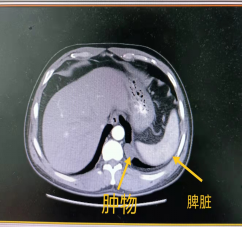

王先生在查体时胸部CT发现左肺下叶基底段有一肿物,遂到我院就诊。副主任医师任军接诊后仔细阅读胸部CT,该肿物位于左肺下叶基底段,向纵隔突出,直径约2.5cm,局部边界毛糙与肺组织不清,初步判断为左肺下叶良性肿物可能性最大,但不排除为纵膈来源和恶性的可能性,需要手术切除方能最终证实。

住院后,完善各项常规术前检查,积极做好手术准备,同时做好肺癌根治术准备。入院第3天,由副主任医师任军、主治医师杨金国为患者行胸腔镜单操作孔肿物切除术,胸部切口长约3厘米,术中发现肿物位于左肺下叶基底段靠近膈肌,完整将肿物切除,送快速病理检查,结果为良性病变,及时告知家属,常规病理结果为支气管源性囊肿,家属悬着的心终于放下了。